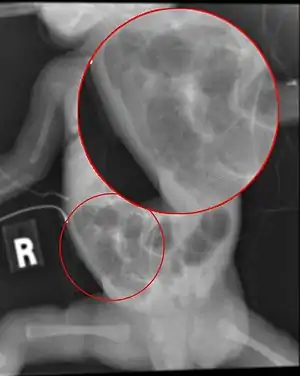

| Radiograph of a baby with necrotizing enterocolitis | |

The diagnosis is usually suspected clinically but often requires the aid of diagnostic imaging modalities, most commonly radiography. Specific radiographic signs of NEC are associated with specific Bell's stages of the disease:[13]

- Specific radiologic signs (pneumatosis intestinalis or portal venous gas

- Severe radiologic signs (pneumoperitoneum)